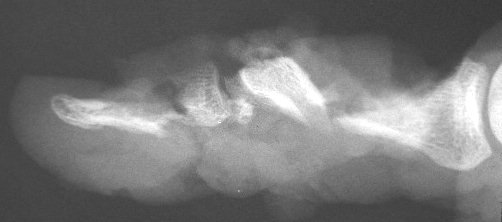

Late result.